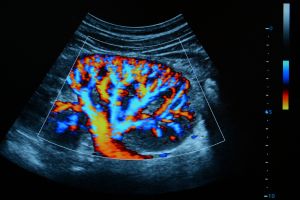

سونوگرافی کالر داپلر

سونوگرافی کالر داپلر یکی از انواع پیشرفته تصویربرداری پزشکی است که بهطور خاص برای بررسی جریان خون در عروق و اندامهای بدن مورد استفاده قرار میگیرد. این روش تلفیقی از سونوگرافی معمولی و تکنیک داپلر رنگی بوده و با ارائه تصاویر زنده و رنگی سرعت و جهت جریان خون را در رگها و شریانها نمایش میدهد. کاربرد اصلی کالر داپلر تشخیص بیماریهای عروقی مانند تنگی یا انسداد عروق، بررسی وریدها و شریانها، ارزیابی سلامت قلب و عروق محیطی و برخی بیماریهای مادرزادی یا اکتسابی است. این تکنولوژی غیرتهاجمی و بیخطر بوده و با دقت بالا به پزشک کمک میکند تا مشکلات گردش خون یا اختلالات عروقی را بهموقع شناسایی و درمان کند.